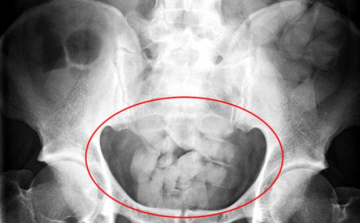

Egy kilo kokaint akart becsempészni Magyarországra a gyomrában

Egy kilogramm kokaint akart Magyarországra csempészni egy brazil férfi úgy, hogy száz kokainkapszulát nyelt le - közölte az Országos Rendőr-főkapitányság kommunikációs szolgálata kedden a rendőrség honlapján.

Száztíz kokainkapszulát csempészett a testében egy férfi Magyarországra

Kábítószer birtoklása miatt indított nyomozást a Készenléti Rendőrség Nemzeti Nyomozó Iroda egy 30 éves bissau-guineai férfi ellen, aki száztíz, kokaint tartalmazó kapszulát csempészett a gyomrában Magyarországra